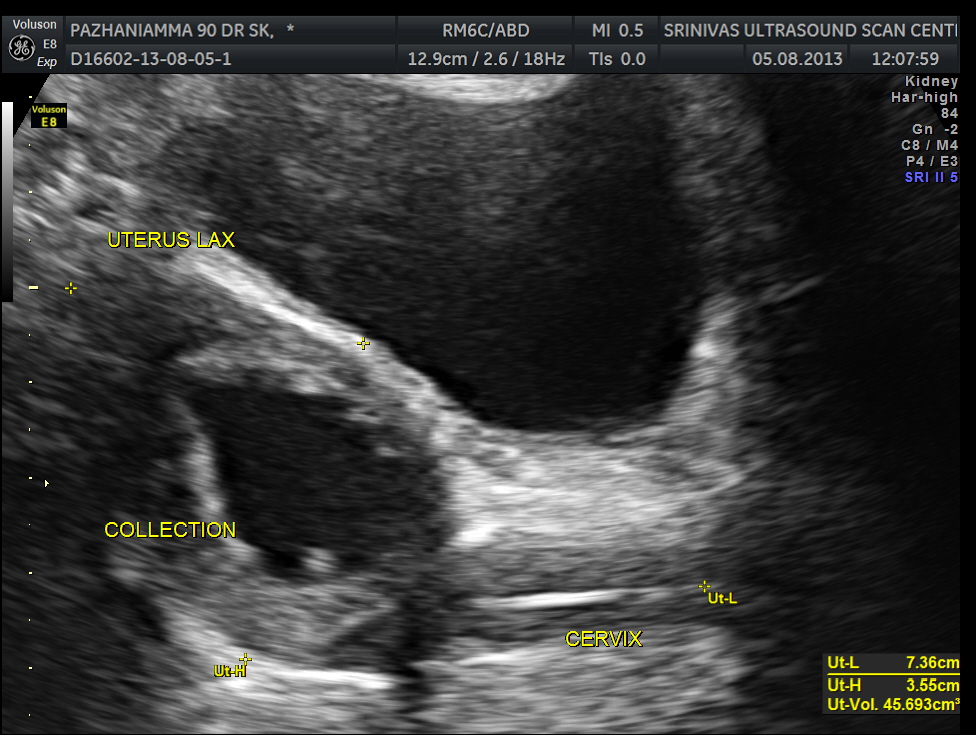

The pelvic scan had a surprise finding. Prominent fluid collection was seen in the endometrial cavity with echogenic cervix. ( She had no symptom of any vaginal bleeding or discharge )

The diagnosis was : acute calculous cholecystitis , cystic duct stones causing a rupture and fluid collection around the GB and loculated sub diaphragmatic collection with reactive mild right pleural effusion . Endometrial fluid collection needed further evaluation.